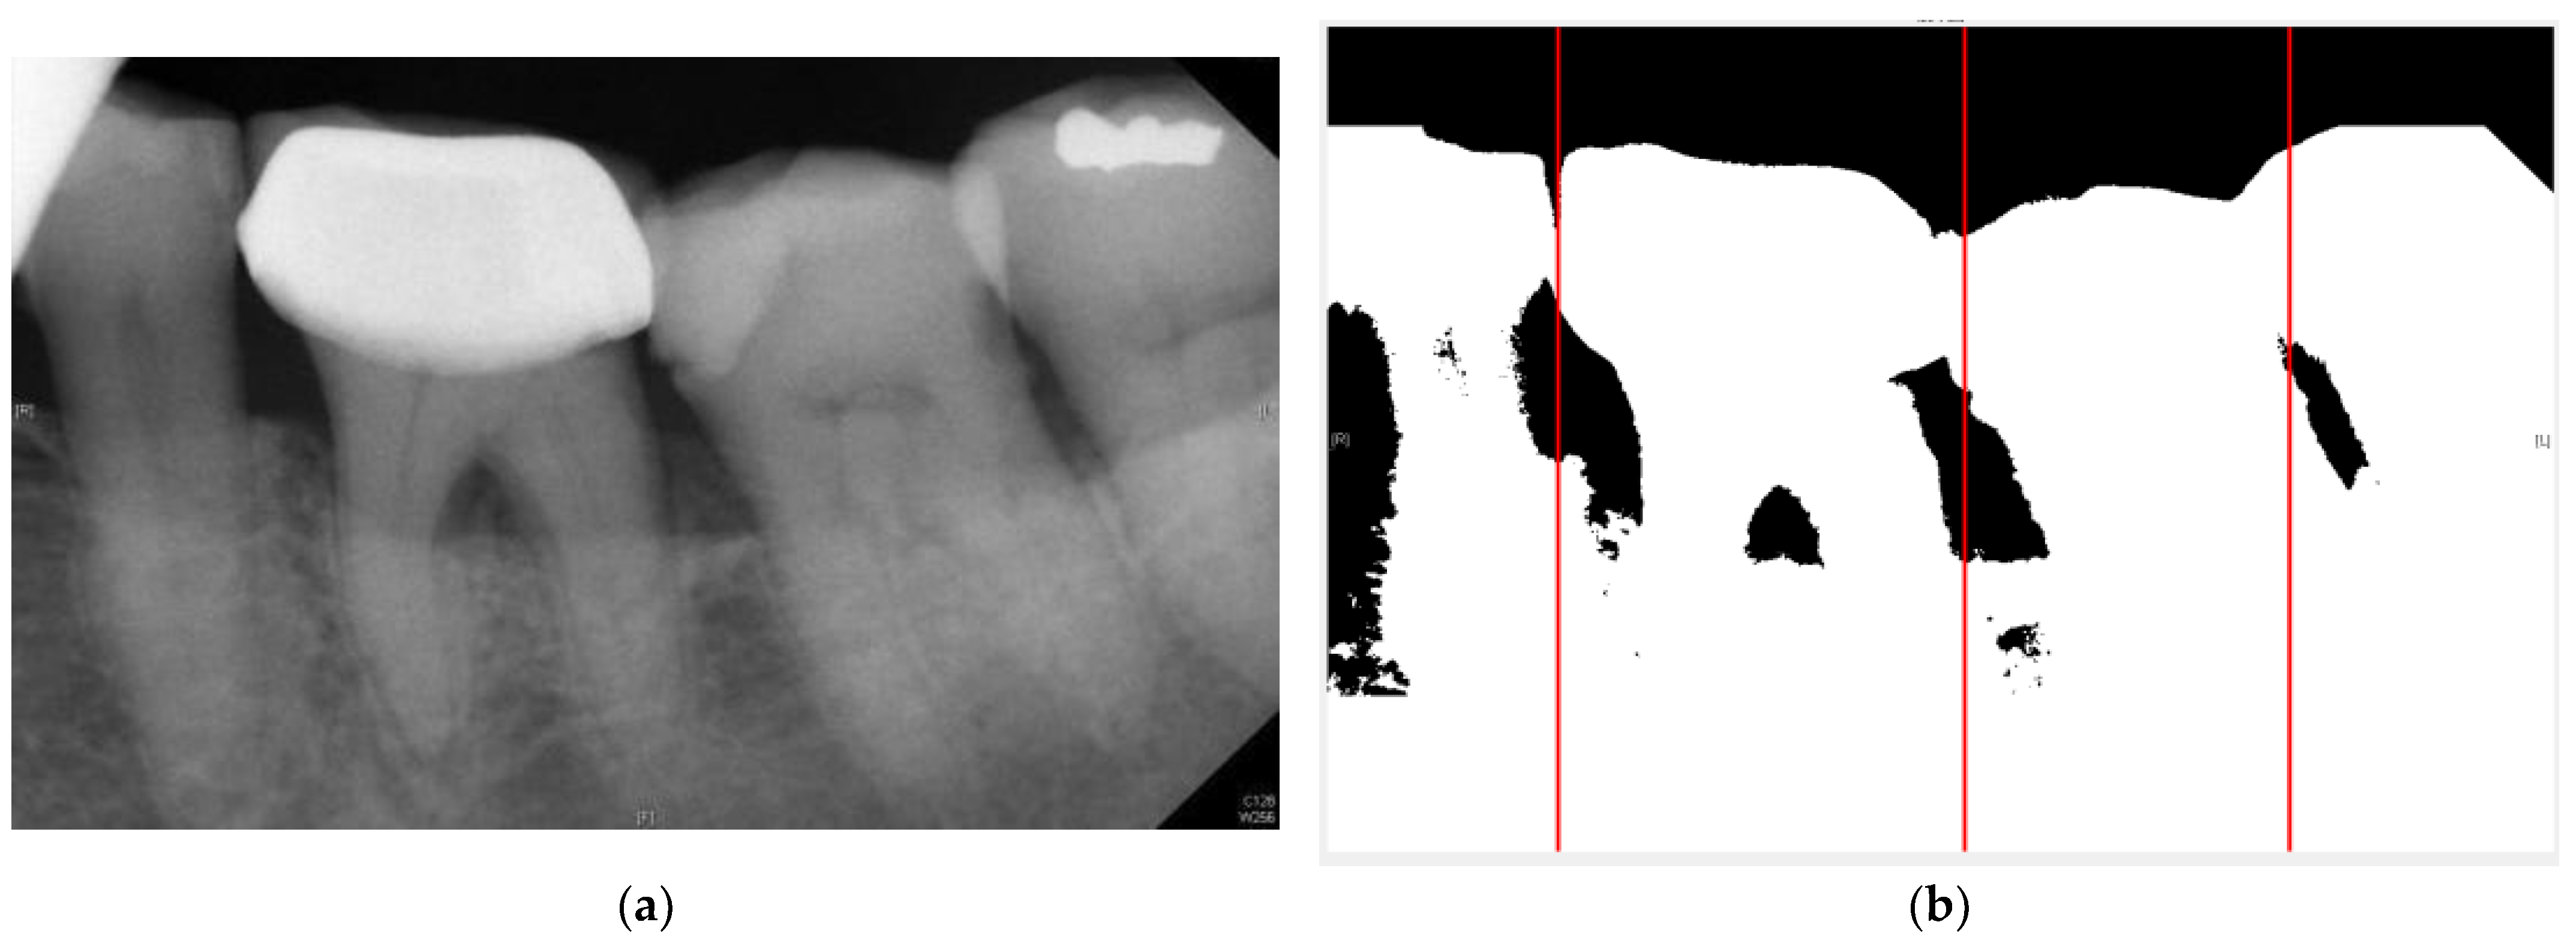

2.1.3. Adaptive Threshold

2.2. Image Segmentation

2.2.1. Vertical Projection